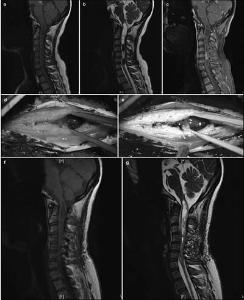

20171023161526 Figure 1 Pre- and postoperative magnetic resonance imaging of intramedullary ependymomas at C1–T1, and intraoperative observations. (a) Preoperative sagittal T1 image reveals spinal cord thickening. (b) T2 image shows high intramedullary signal intensity at C1–T1, but no signal at either end. (c) Enhanced scanning reveals distinctive tumor enhancement. (d) Intact tumor with clear boundaries, as viewed under a microscope. (e) Tumor images, viewed via fluorescence microscopy, showing a distinctive basal structure. Sagittal T1 (f) and T2 (g) images, 3 months after surgery, do not show tumor residuals or relapses.

20171023161638 Figure 2 Pre- and postoperative magnetic resonance imaging of intramedullary ependymomas at C2–T2, and intraoperative observations. (a) Preoperative sagittal T1 image reveals spinal cord thickening. (b) T2 image shows high intramedullary signal intensity at C2–T2, but no signal at either end. (c) Enhanced scanning reveals distinctive enhancement of the tumor mass and cyst wall. Tumor ends, as micrographed using white light (d) and fluorescence (e). (f) Cysts at the tumor ends, microscopically probed with white light, do not show the tumor. (g) Distinct cyst walls are evident under fluorescent illumination, revealing a suspicious tumor that was removed. At 3 months, the sagittal T1 (h) and T2 (i) images and the enhanced scan (j) reveal no evidence of tumor residuals or relapses.

20171023161742 Figure 3 Intramedullary ependymomas at C3–C7, and tumor-associated stroke. (a) Preoperative T1 image showing spinal cord thickening and cysts in the septum. (b) Preoperative T2 image of a mass at C3–C7 and cysts in the septum. Stroke was not detected. (c) Preoperative enhanced magnetic resonance image showing an intramedullary tumor as a distinctive mass at C3–C7. Stroke enhancement was undetected. (d) Indistinct tumor images, intraoperatively, under fluorescent illumination. (e) Distinct intraoperative image of a tumor under the microscope. (f) Intraoperative and 1-month postoperative T1 images show the absence of tumor residuals or relapses. (g) T2 images, 1 month after surgery, show the absence of tumor residuals and relapses.